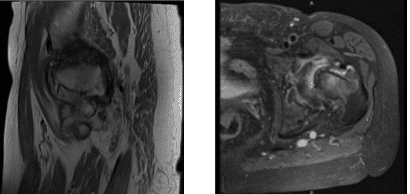

MRI Left hip non-contrast

In left hip MRI, Bone and Joint there is severe joint space narrowing the left hip joint with bone-on-bone contact. There is subchondral bone marrow edema subchondral cyst in the lateral acetabulum and lateral aspect of the femoral head with bone marrow edema extending into the femoral neck and intertrochanteric fossa.

There is flattening of the femoral head. There is extensive full-thickness cartilage loss. There is a moderate left hip joint effusion with synovitis. There is diffuse tearing of the labrum. The Tendons/Muscles have visualized tensor fascia lata, rectus femoris, hamstring tendons and iliopsoas intact.

No iliopsoas bursitis is noted. The gluteus Medius and minimus insertions are intact. No trochanteric bursitis is noted. The ischiofemoral interspace and quadratus femoris muscles are intact.

The piriformis muscles and the common rectus abdominis, and adductor aponeurosis are intact. The visualized sciatic nerve is intact. There is marked scoliosis.

The nerves have a fat plane surrounding the sciatic nerve. In Pelvis and Contralateral Hip: The pubic symphysis is intact. There is marked osteoarthritis in the right hip joint. The visualized pelvic visceral structures appear normal. No enlarged lymphadenopathy. No free fluid in the pelvis.

The periarticular subcutaneous tissues are unremarkable. It has a severe osteoarthritis in the left hip joint with associated subchondral bone marrow edema in the femoral head and neck and flattening of the femoral head. Diffuse tearing labrum. Moderate left hip joint effusion.